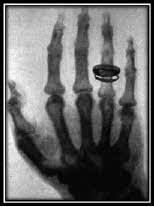

Las radiaciones también se pueden producir de forma artificial, En 1895, el físico Roëntgen, cuando experimentaba con rayos catódicos, descubrió el primer tipo de radiación artificial que ha utilizado el ser humano: los rayos X.

A partir de otoño de 1895, Wilhem Conrad Roentgen se interesó profundamente por los experimentos con el tubo de rayos catódicos de Hittorf y Crookes, repitiendo ciertos experimentos de Lenard sobre la fluorescencia del platinocianuro de bario fuera del tubo de vacío.

Unos de los pioneros británicos del uso de rayos X para localizar cuerpos extraños fue el radiólogo de Birmingham, John Hall Edwards, que publicó artículos sobre este tema, incluida una carta en la revista médica British Medical Journal en 1896.

Una fiebre de Röntgen real se propagó por todo el mundo. El uso comercial de la tecnología de rayos X convirtió a la ciencia en una especie de espectáculo. No existía la necesidad de ocuparse con sensatez de la peligrosa radiación.